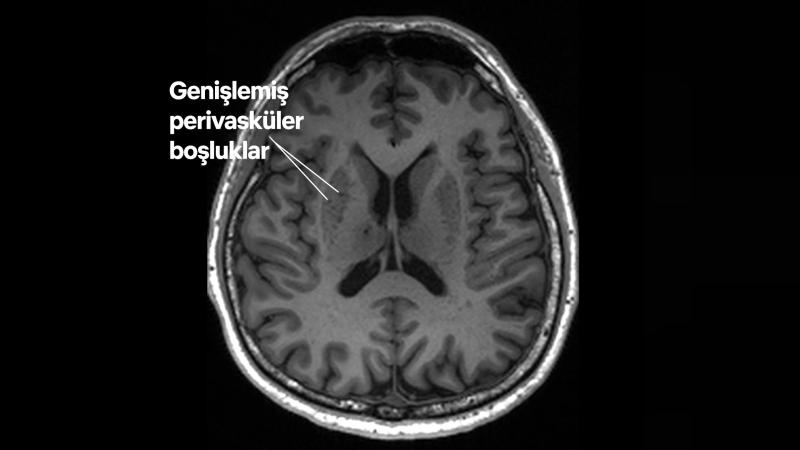

Genişlemiş perivasküler boşluklara sahip bir hastanın manyetik rezonans görüntüleme taramasında bu boşluklar, beyin merkezinin etrafındaki koyu gri bölgelerde koyu lezyonlar şeklinde görülüyor (NTU LKC Tıp Fakültesi)

Araştırmacılar MR taramalarında görülebilen, beynin tıkalı drenaj alanlarının, büyük bir beyin hasarı gerçekleşmeden önce Alzheimer'ın erken göstergeleri olabileceğini tespit etti.

Beyindeki bu doğal "drenajların" (zararlı atıkları temizlemek için yol görevi gören küçük kanallar) Alzheimer'ın erken belirtilerini gösteren kişilerde tıkanma olasılığının daha yüksek olduğunu buldular.

Hakemli dergi Neurology'de yayımlanan çalışmaya göre "genişlemiş perivasküler boşluklar" diye adlandırılan bu drenajlardaki tıkanıklıklar, demansın önemli bir erken sinyali olarak işlev görebilir.

Singapur Nanyang Teknoloji Üniversitesi'nden (NTU Singapur) nörolog Nagaendran Kandiah, "Bu beyin anomalileri, bilişsel gerilemeyi ölçmek için yapılan rutin manyetik rezonans görüntüleme (MR) taramalarında görsel yolla tespit edilebilir" diyor.

Dr. Kandiah şu ifadeleri kullanıyor:

Bunların tespit edilmesi, ek testler yapıp para ödemek zorunda kalmadan, Alzheimer'ın daha erken teşhisinde mevcut yöntemleri tamamlayabilir.

Araştırmacılar drenaj sistemi verimsiz hale geldiğinde, bu boşlukların MR taramalarında tespit edilebilecek şekilde genişleyebileceğini söylüyor.